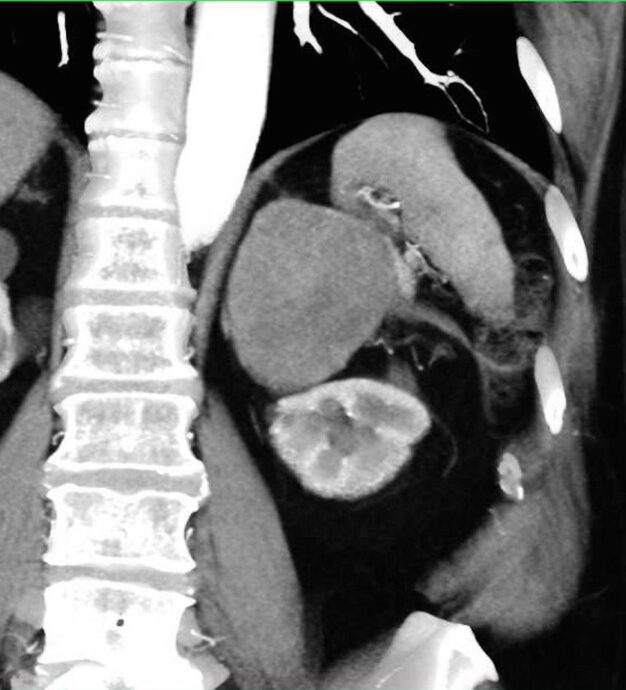

TC DE GLANDULAS SUPRARRENALES.

La hemorragia suprarrenal es una entidad infrecuente que puede ser uní o bilateral.

Las causas de hemorragia suprarrenal se dividen en traumáticas (la mayoría unilaterales y derechas) y espontaneas, agudas y crónicas.